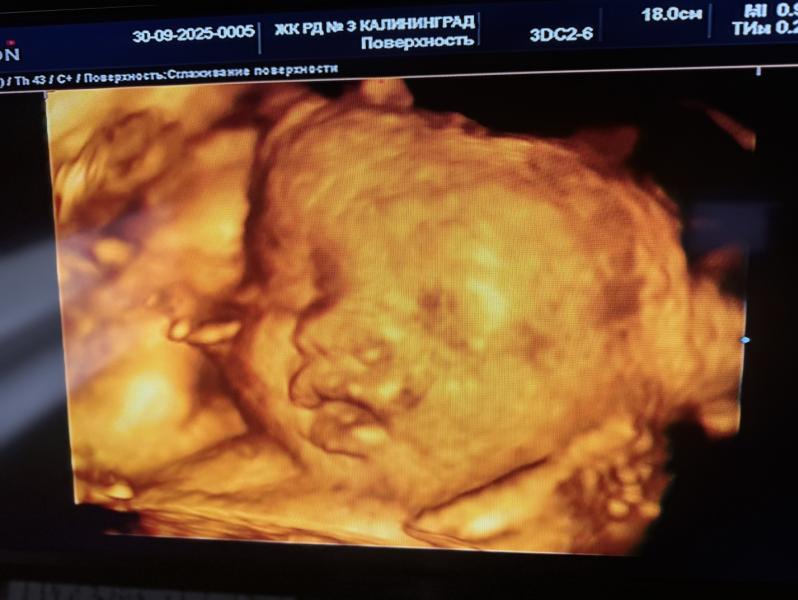

Бонусом мне вчера на узи фото губастой девчонки дали ))) ♥️🥹